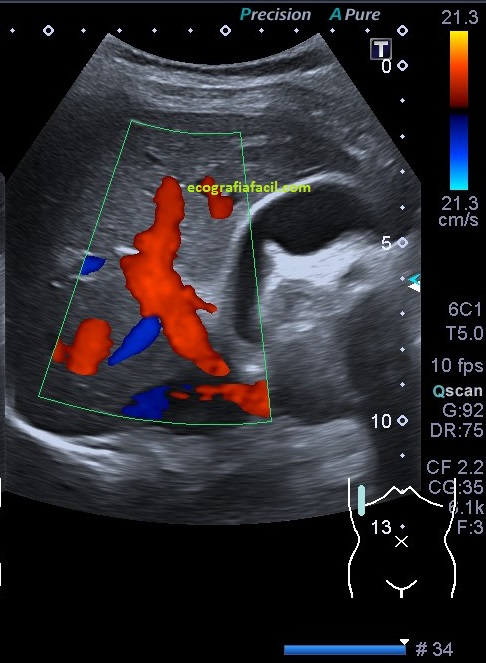

Lo realmente importante viene en la imagen 6, se llama Bi Flow, es una técnica «no doppler» y permite estudiar flujos sin tener en cuenta aspectos técnicos como la angulación, es decir, si hay vascularización, la vamos a detectar, suprime el tejido para visualizar el flujo real sin sobrescribir los vasos. Esto me parece absolutamente revolucionario. Es una técnica sustituta del modo angio y podría ser sustituta del modo angio habitual.